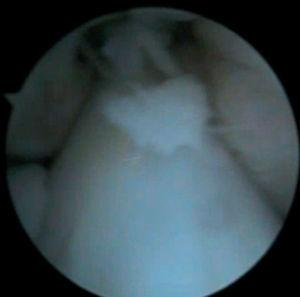

Figura 3 RM. Imagen potenciada en T2 con supresión de grasa. Lesión condral amplia en rótula, faceta externa y cresta condral.

Figura 4 Artroscopia. Lesión condral amplia en rótula, faceta externa y cresta condral.

• Lesión condral amplia en faceta externa y cresta de rótula, de grosor parcial.

• Lesión condral anfractuosa extensa, con fragmentos inestables en cresta de la rótula y en faceta externa, de grado III.